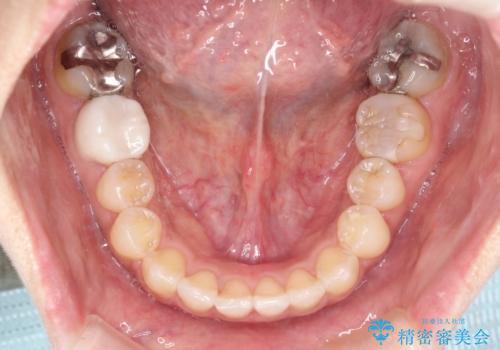

前歯のガタつきをマウスピース矯正で改善! 驚きの効果を体験しよう

- 前歯のガタツキが気になると来院されました。

マウスピース矯正治療を選択しました。

奥歯の噛み合わせは綺麗に噛んでいたため、前歯の叢生(でこぼこ)に集中して治療するように計画しました。

奥歯の噛み合わせは整っていたため、前歯の並びを美しく修正することに専念できました。

前歯のガタツキを改善する治療法として、マウスピース矯正が適していることが多いです。

マウスピース矯正は、金属製のブラケットやワイヤーを使用せずに、透明なマウスピースを装着して歯を移動させる方法です。そのため、目立たず、痛みも少ないです。